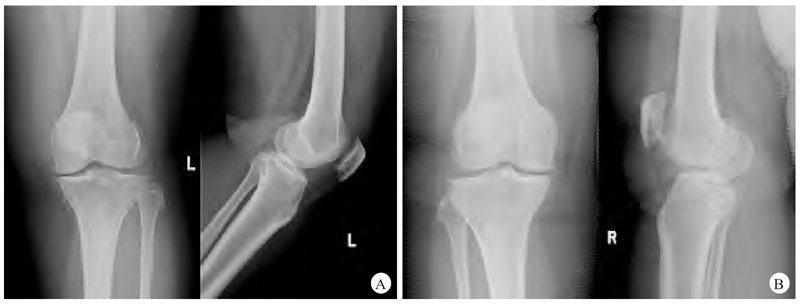

患者肥胖体形,身高145cm,体重72kg,体重指数34.2kg/m2,双膝部稍肿胀,局部皮肤完整,皮肤颜色、温度正常,双膝关节内侧膝关节间隙压痛明显,双膝关节活动度0°~140°,双下肢肌力及肌张力正常,双膝磨髌试验(−),过伸过屈试验(+),抽屉实验(−),侧方应力试验(−),麦氏试验(+),双下肢末梢血液循环及感觉未见明显异常,足背动脉均可触及。X线检查显示双膝内侧关节间隙减小(图1)。

图1 患者术前X线表现

A. 左膝关节正、侧位X线片显示左膝关节内侧间隙明显减小;B. 右膝关节正、侧位X线片显示右膝关节内侧间隙明显减小;C. 双下肢全长正位X线片显示双膝关节内侧间隙明显减小,左膝内侧间室已骨对骨摩擦。